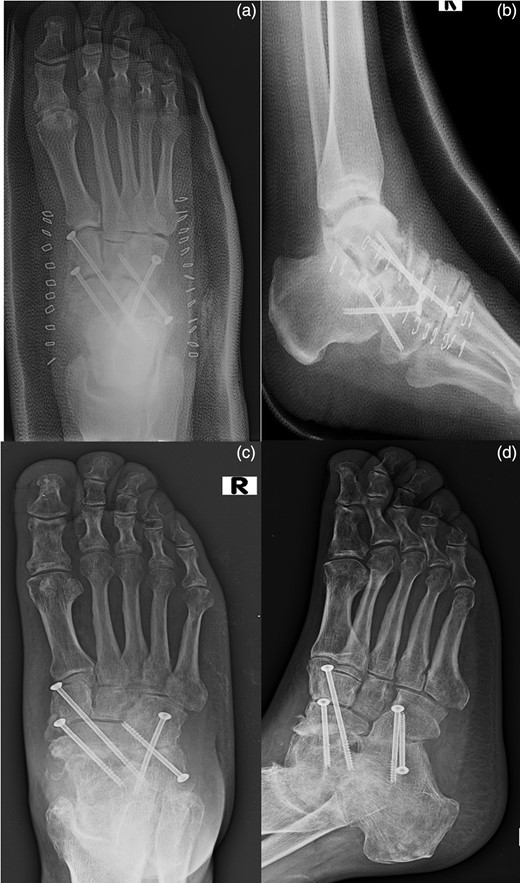

The patient underwent a first-time surgical repair. Abundant washing of the lacerated wound with saline solution and chlorhexidine was done. Injuries of dorsalis pedis artery, tibialis anterior tendon, estensor digitorum longus tendons, peroneus tertium tendon were revealed, with the loss of talus head and with a complex lesion of the talonavicular ligament. Tendinous structures damaged were surgically sutured and subsequently an antibiotic-loaded cement spacer was positioned into the bone gap to re-establish the joint congruence. The foot was put in a cast and kept non-weight bearing for 8 weeks (Fig. 2).

An image of the foot before the first-time surgical repair reveals the injuries of dorsalis pedis artery, tibialis anterior tendon, estensor digitorum longus tendons, peroneus tertium tendon, with the loss of talus head and with a complex lesion of the talonavicular ligament. (a) Tendinous structures damaged were surgically sutured and subsequently an antibiotic-loaded cement spacer was positioned into the bone gap to reestablish the joint congruence (b). AP (c) and lateral (d) radiographs of the foot in the cast after the surgical time.